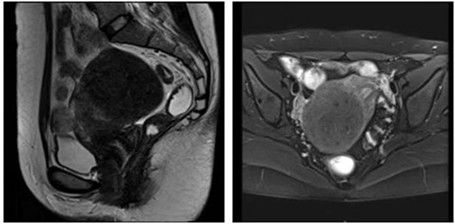

·盆腔MRI:子宫右后壁肿块,考虑肌瘤(80mm*72mm*67mm);盆腔少许积液 。